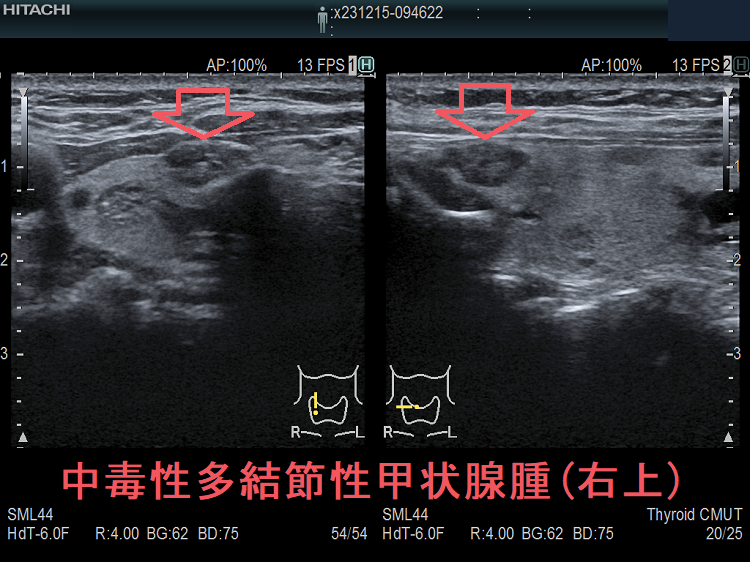

医師が多結節性甲状腺腫を発見した場合、甲状腺の超音波検査を受けることになるでしょう。超音波検査の結果に応じて、結節に癌性があるかどうかを確認するために細針吸引生検が行われる場合があります。

多結節性甲状腺腫の中には有毒なものもあります。これは、甲状腺ホルモンを過剰に生成することを意味します。これにより甲状腺機能亢進症が引き起こされます。甲状腺機能亢進症は、甲状腺ホルモンの生成を停止する薬物療法、放射性ヨウ素、または甲状腺組織の除去によって治療できます。

したがって、医師は甲状腺超音波検査を指示する場合があります。超音波検査では、音波を使用して甲状腺の写真を撮影します。これは、医師が結節が体液で満たされているか、石灰化があるかを判断し、結節の数と場所を確認し、癌の可能性がある結節を特定するのに役立ちます。